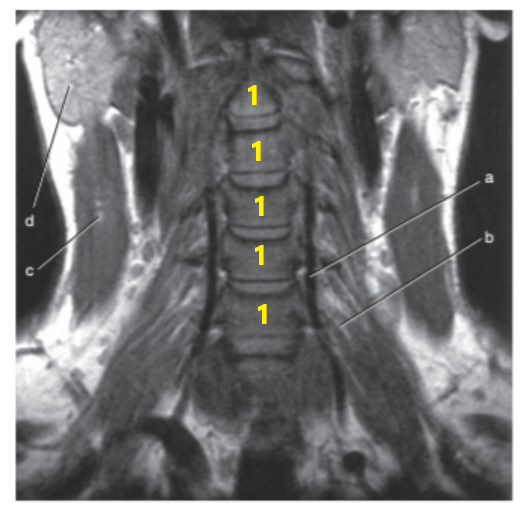

What is # 1's ?

Cervical spine